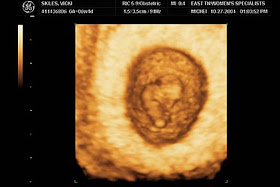

6 haftalık bebeğin görüntüsü nasıldır?

| görüntü 1 |